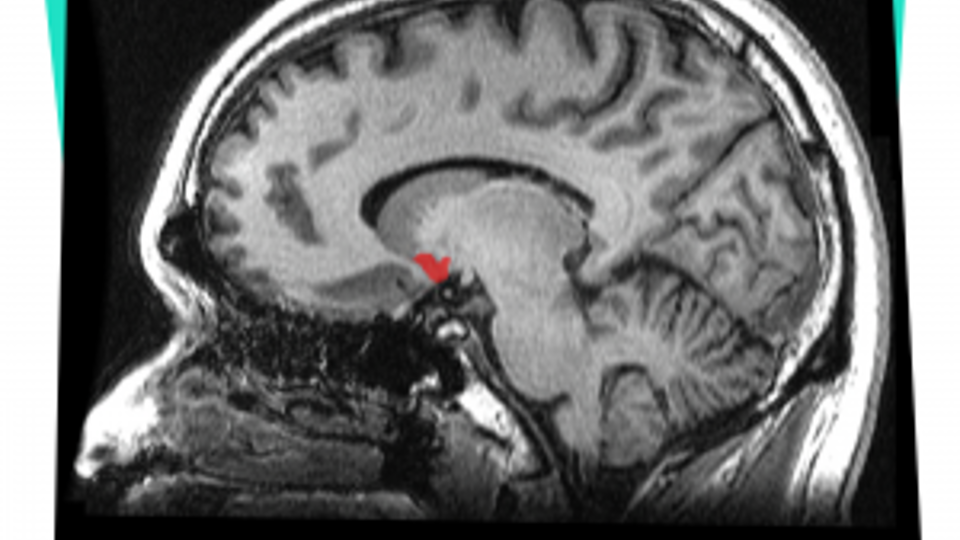

Daarnaast heeft alcohol een indirect effect op dopamine in het brein. Dopamine is een stimulerende neurotransmitter. In een specifiek hersengebied, genaamd de nucleus accumbens (zie afbeelding), zorgt dopamine voor een belonend effect. Dopamine geeft je een fijn gevoel. Het komt ook vrij bij eten en seks. Alcohol zorgt dus voor een beloning in het brein. Hierdoor heeft alcohol een verslavende werking. Als de nucleus accumbens gestimuleerd wordt door veel dopamine, is er sprake van veel genot. Maar aan de andere kant, als iemand opeens minder alcohol gaat drinken en de nucleus accumbens minder dopamine binnenkrijgt, ontstaan er ontwenningsverschijnselen zoals vermoeidheid en somberheid.